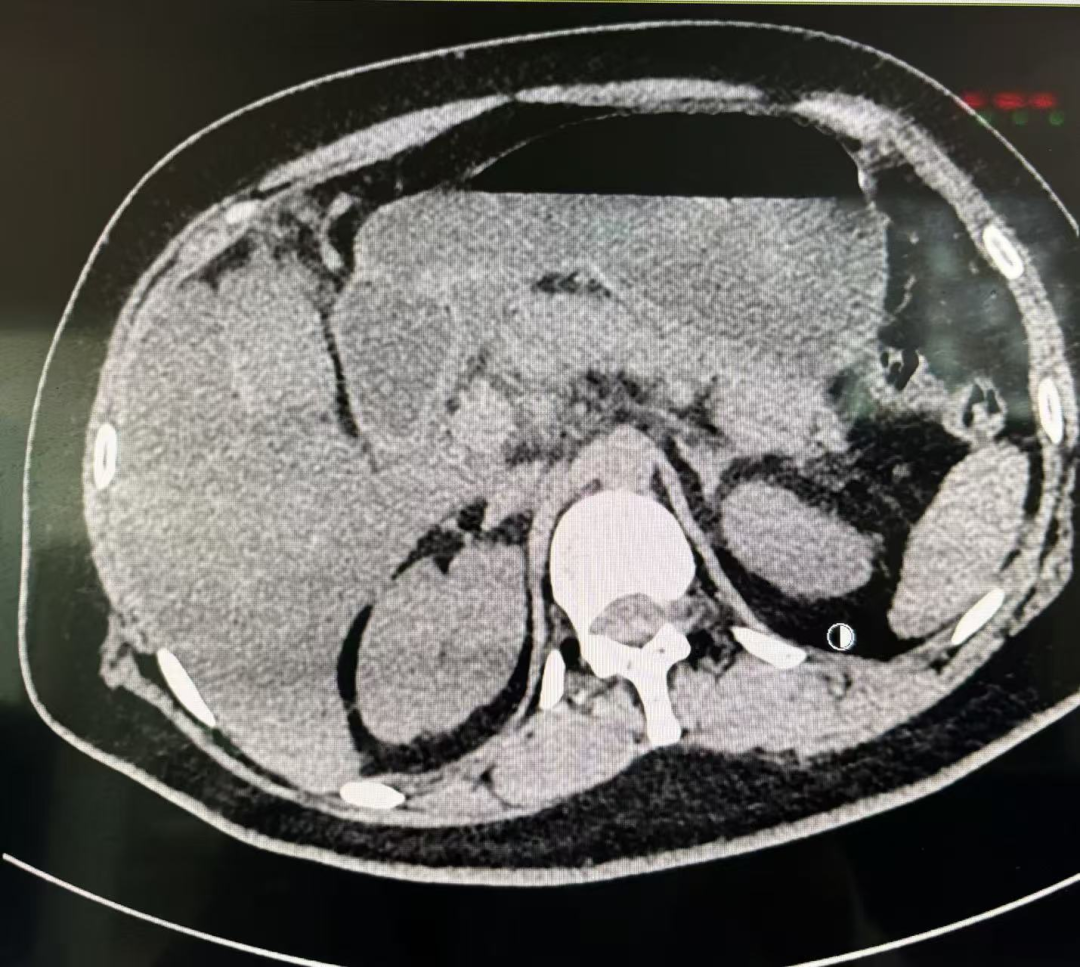

外院及该院的紧急检查结果令人触目惊心:随机血糖飙升至惊人的 88.9mmol/L,血酮显示“HIGH”;动脉血气 pH 值低至 7.14,属于严重酸中毒,碳酸氢根仅 5mmol/L;同时伴有肾功能急性损伤,肌酐达 280.6μmol/L,淀粉酶和脂肪酶显著升高,提示胰腺损伤。腹部 CT 及彩超进一步证实胰腺肿胀、渗出,且存在重度脂肪肝。患者病情极其复杂危重,生命垂危。